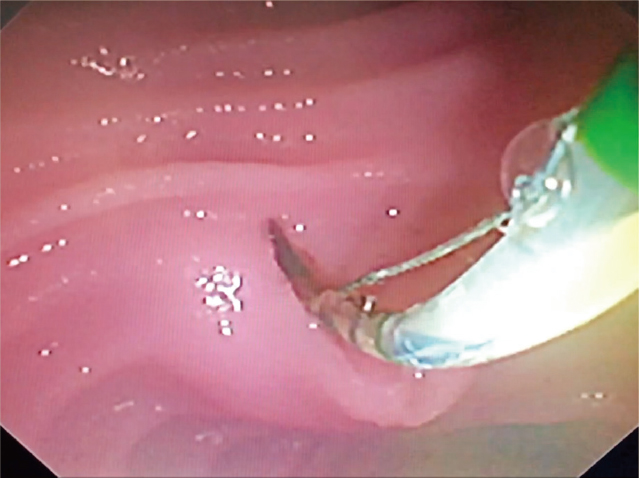

ERCP関連手技の中で,達人Peter Cotton教授をもってしても,“ESTは内視鏡医によってルーチンに行われる最も危険な手技”とされている 21).そのESTの教育としてASGEは早くから学会主催のハンズオンセミナーでMatthesらが開発したウエットモデル 22)を用いた教育を行ってきた.これはブタの食道から十二指腸までの臓器にヒトの乳頭付近の十二指腸に穴を開け,そこにカニュレーションのための穴を開けた鳥の心臓を縫い付けた.私も実際に米国でハンズオンで施行した印象は,ESTモデルがない中では十分満足のいくものであったことを覚えている.私はこれに刺激を受けて,後日ESDの大腸モデルを利用した筒型のESTと内視鏡的乳頭切除術(endoscopic papillectomy:EP)モデルをアムコ社と共同で作製した(Figure 7) 23).

EST/EP教育用ファントム(アムコ社製).

b:膨隆させたのちにスネアでEP施行.

d:EP後内視鏡.

e:初期研修医に対するEST教育の実際(左:内視鏡像,右:施行中の外観).